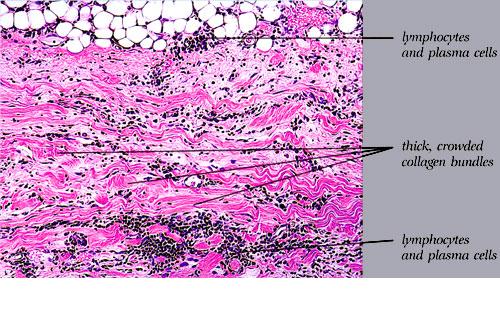

Morphea_late stage = صلابة الجلد مرحلة متأخرة

Morphea_late stage = صلابة الجلد مرحلة متأخرة Morphea In morphea, or circumscribed scleroderma, the lesions usually are limited to the skin and to the subcutaneous tissue beneath the cutaneous lesions. Occasionally, however, the underlying muscles and rarely the underlying bones are also affected. Morphea may be divided according to morphology and distribution of lesions into […]